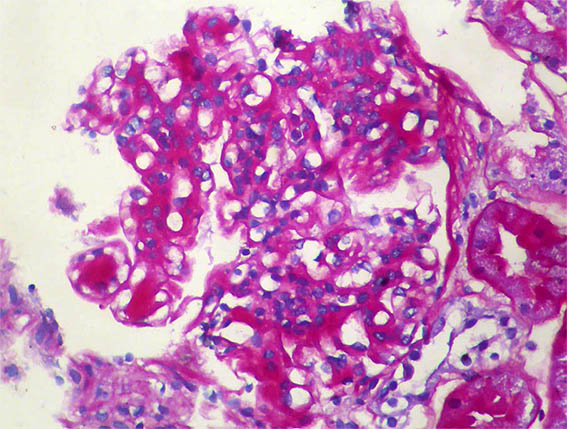

Figure 1. H&E, X400.

Figure 2. H&E, X400.

Figure 3.

H&E, X400.